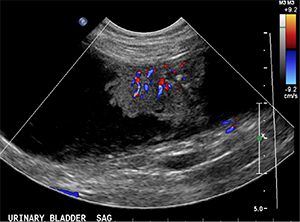

Abdominal ultrasonography results are shown below:

- At least 3 florid-like urinary bladder masses are seen in the dorsal and ventral wall. The largest measures 4.3cm x 1.5cm x 2.4cm, with pinpoint hyperechoic specks and marked vascularity on color flow Doppler. This is consistent with primary urinary bladder neoplasia, likely a transitional cell carcinoma (TCC). The proximal urethra and prostate look normal.